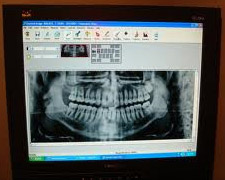

Dental Radiographs

Our office utilizes modern digital x-rays, not film x-rays. This means that a tiny sensor is placed gently in the mouth and the x-ray image 'pops' immediately on the computer screen. Kids are encouraged to make a 'puzzle' on the screen. Kids really get excited as we show them how we can zoom in, enlarge and colorize the pictures! Little does the child know that this method utilizes at least 60% less radiation than the old chemical kind.